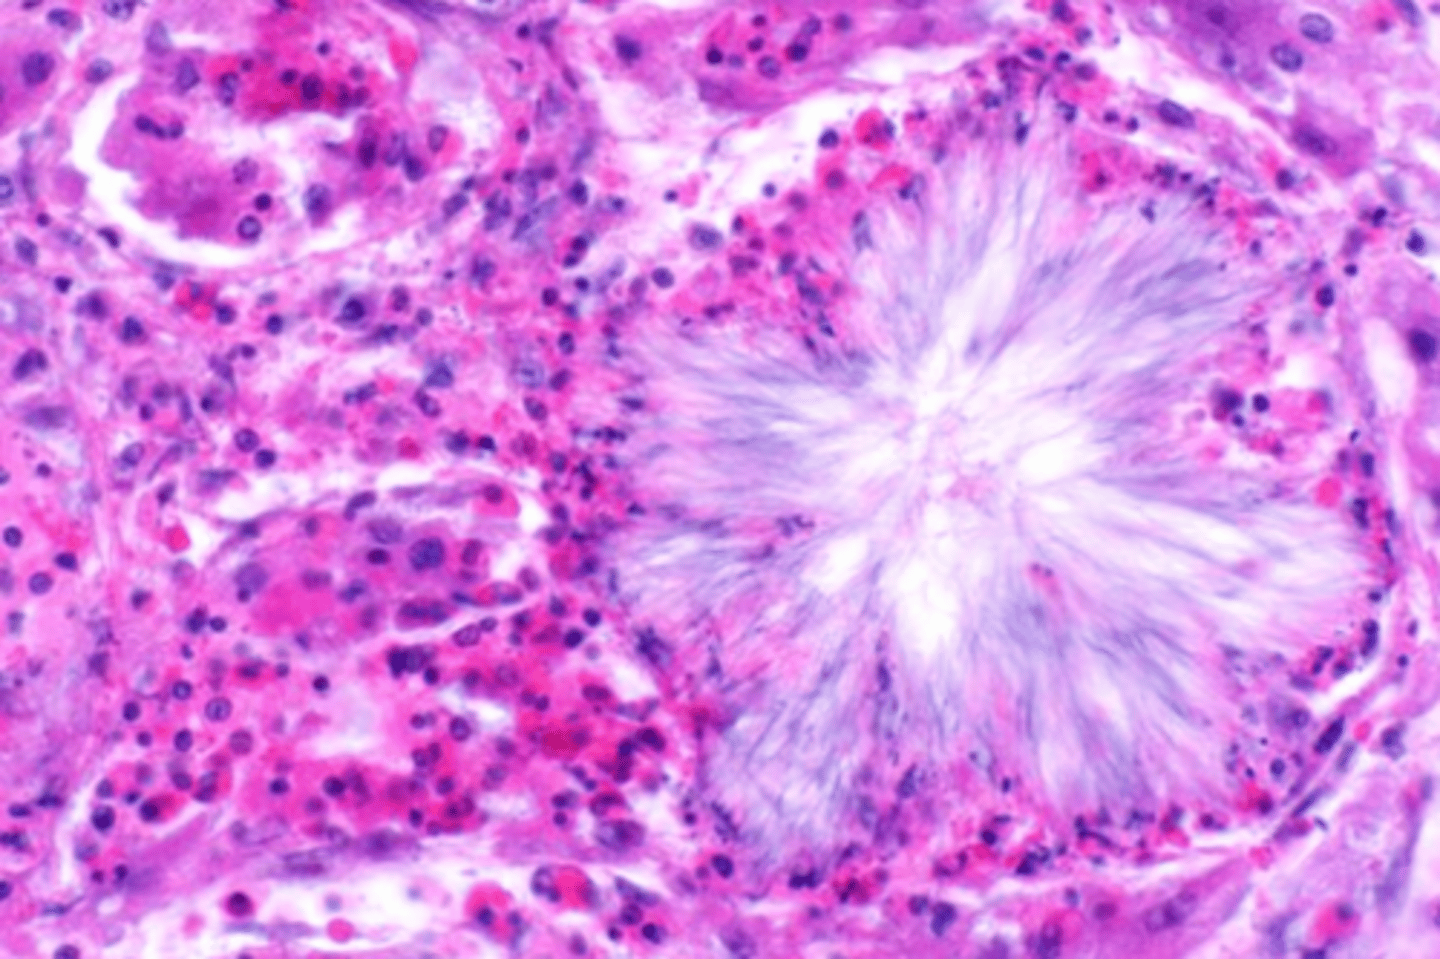

amyloid

describe the extracellular accumulation